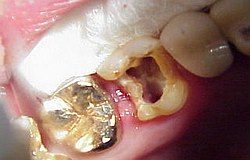

Situation am Patient betrachtet

Wird nichts mehr empfunden so ist er tot und das tote Gewebe muss schnellstens aus dem Zahn entfernt werden (Wurzelkanalreinigung) bevor es im Zahn verfault und zu starken Schmerzen bis hin zur dicken Backe (Zyste) führt. Obwohl im Bild zur Verdeutlichung dargestellt ist eine Aufbereitung des Wurzelkanals (Nervnadel ragt über Wurzel hinaus ) über die Wurzel in den Kieferknochen bei der Zahnwurzelbehandlung natürlich nicht erwünscht. Um dies zu vermeiden müssen während der Wurzelbehandlung Röntgenaufnahmen angefertigt werden, die die ungefähre Länge der Wurzel berechnen lassen. Besser noch lässt sich die Länge der Wurzel elektronisch bestimmen .(Auf Wunsch Privatleistung). Ist die Wurzel an Ihrem Ende weit geöffnet kann es trotz aller Vorsicht zu einem ungewünschten Überaufbereiten und zu einer Überfüllung der Wurzel kommen. Dies beeinträchtigt dann oft den Erfolg. html Text zum Ausdrucken als pdf Datei. Falls über die Wurzelspitze hinaus in den umliegenden Knochen bereits Eiter aufgetreten ist und dieser den Knochen um den Zahn auflöst (das sieht man im Röntgenbild), so muss die infektiöse Wurzelspitze und die darum liegende Zyste entfernt werden .Im Prinzip ähnlich einem Pickel ausdrücken. Sobald der Druck (Eiter) dann heraus kann, geht sehr schnell der Schmerz bzw. auch die dicke Backe zurück. Der Vorgang nennt sich Wurzelresektion oder Apektomie. Die moderne Wurzelbehandlung umfasst Nickel-Titan-Feilen mit drehmomentregulierten Motoren gegen Instrumentenbruch, elektronische Längenmessung, Langzeit-provisorische Wurzelfüllungen mit provisorischen Langzeit-Füllungen. Alles leider Dinge die nicht in der Kassenleistung enthalten sind. So bleiben für den Patienten Kosten von ca. 60-480 EUR (je nach Schwierigkeit ) pro Kanal Aus manchen spezialisierten Prominentenpraxen wurde mir schon von Preisen bis zu 1200 EUR pro Kanal berichtet.